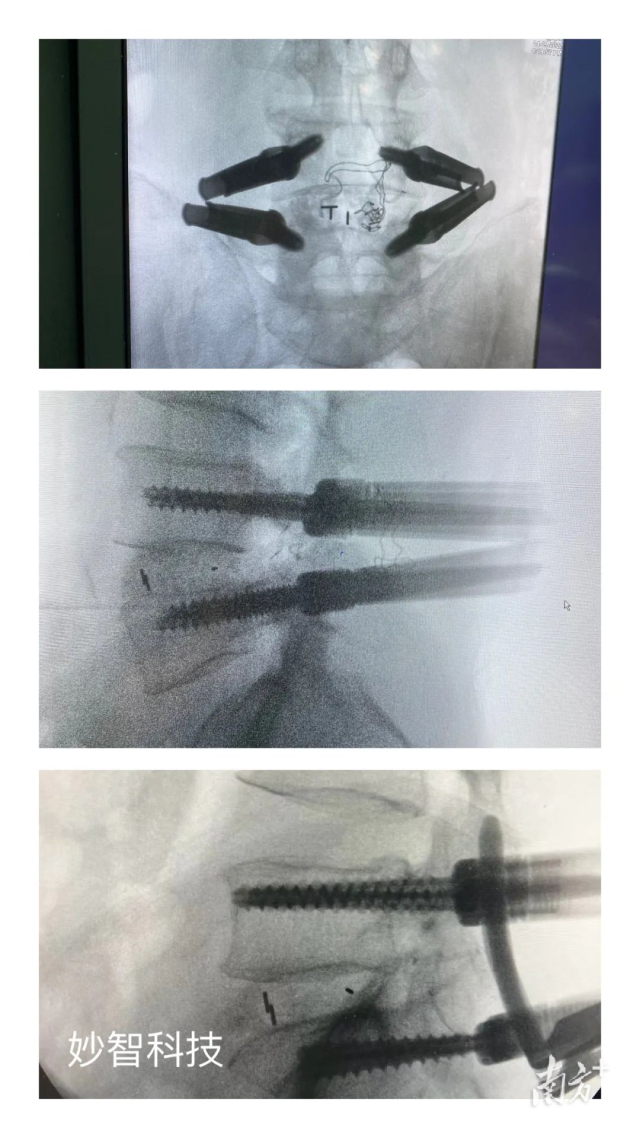

妙智科技研發(fā)的骨科機器人在臨床中試驗

由於新型醫(yī)療器械壹般研究周期較長,目前,妙智科技研發(fā)的骨科機器人仍在臨床試驗階段。截至2022年底,妙智科技已經完成了近50例臨床病例,預計今年計劃將完成取證並開始售賣。